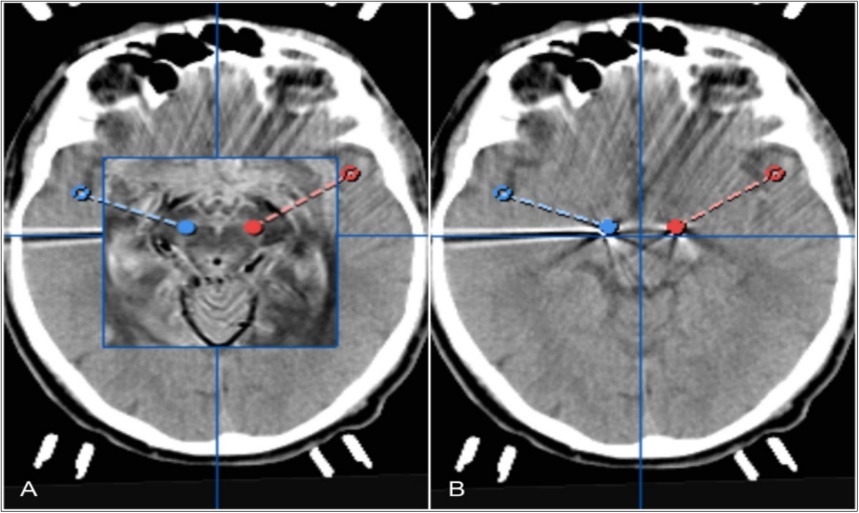

The procedure was performed without any complications. Postoperative cranial CT imaging revealed proper placement of both electrodes in the central part of STN (Figure 2). After fusion with the preoperative stereotactic plan, both electrodes were seen in the correct position of the STN (Figure 2). Electrodes were postoperatively activated bilaterally for continous stimulation with the wireless iOS mobile programming platform (Table 1). The patient experienced strong improvement of bradykinesia and rigidity under stimulation of the anterior segmented electrode (130Hz, 0.5mA). He was able to speak and walk without any problems. The apomorphin medication was stopped. L-dopa medication was reduced. Simultaneous activation of all segments around the circumference of the electrode caused the patient to suffer dysarthria and motor symptoms.

Figure 2.Pre- and postoperative computertomography merge showing tips of electrodes fused to bilateral trajectories of planned STNDBS